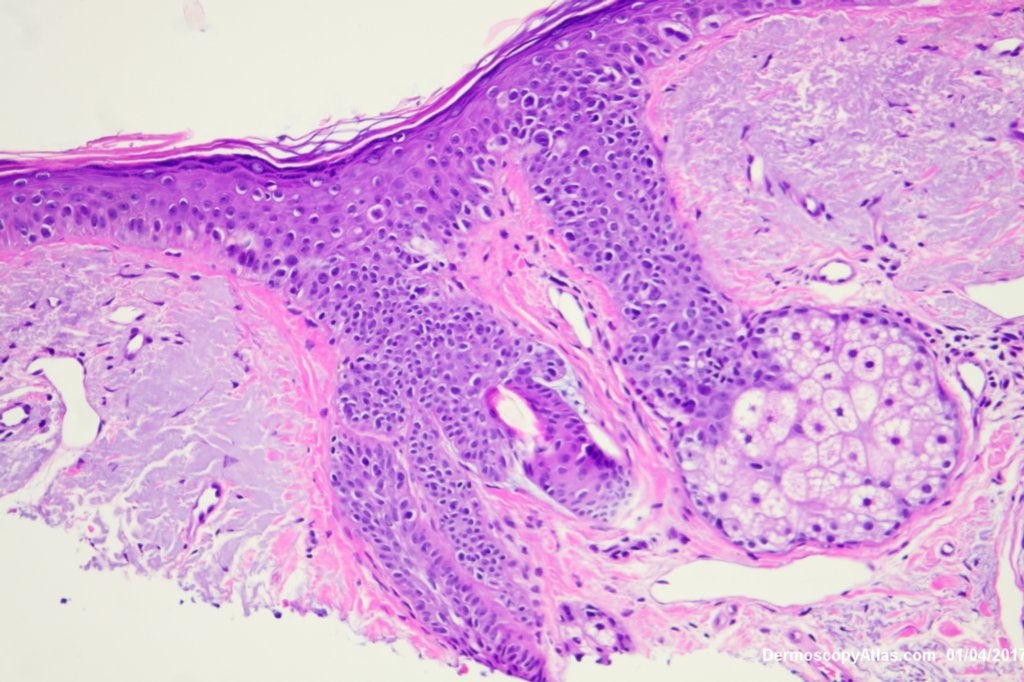

Description: Lentiginous proliferation of atypical melanocytes

The Dermatoscopy shows partial grey circles and the histology shows a lentiginous proliferation of atypical melanocytes involving the hair follicles.